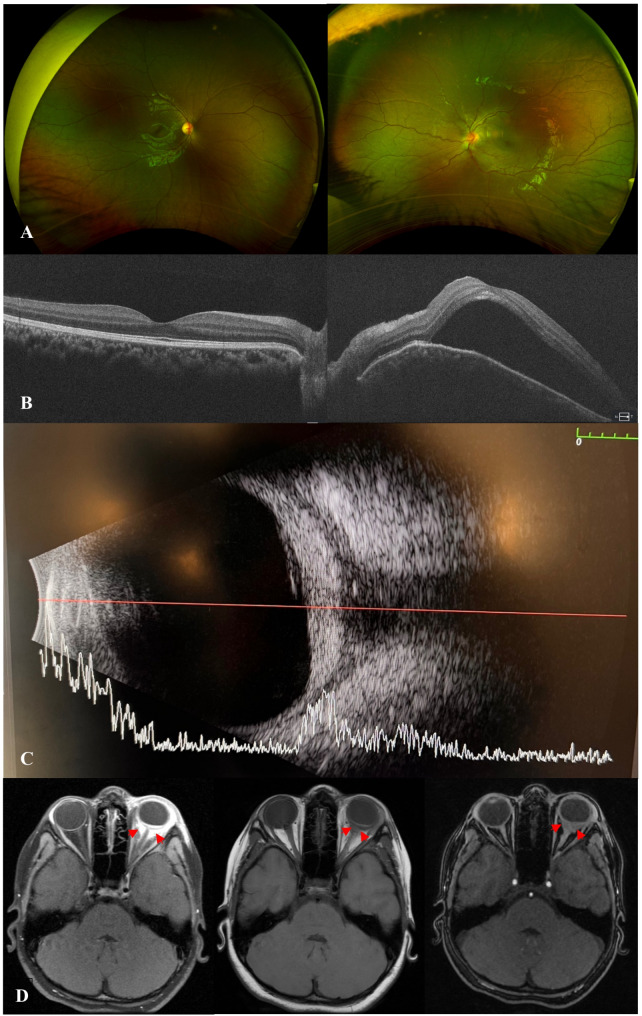

Observations: A 7-year-old girl presented with proptosis, painful eyelid swelling, and restricted extraocular movements (EOM) of her left eye (OS). Visual acuity (VA) was 20/20 in right eye (OD) and counting fingers (CF) at 1 foot in OS. Slit lamp examination revealed 2 + anterior chamber (AC) cells, optic disc edema (ODE) with elevated appearance of macula in OS. Optical coherence tomography (OCT) showed significant subretinal fluid (SRF) in macula, B-scan ultrasound (US) demonstrated T-sign in OS. Orbital MRI was also consistent with posterior scleritis and periorbital inflammation. Extensive systemic work-up was unremarkable. Thus, the patient was started on intravenous methylprednisolone (IVMP) 30 mg/kg/day for 3 days, along with topical therapy in OS, which led to an improvement of proptosis, EOM restriction, AC cells, as well as ODE and SRF in macula in OS. Fluorescein angiography (FA) showed leakage from optic disc in OS. The patient was then switched to oral prednisone with slow tapering and started on methotrexate (MTX). Given the recurrence of proptosis and painful eyelid swelling on systemic steroid tapering, serum IgG4 levels were ordered and found to be elevated at 149.9 mg/dL (range, 1-99). Therefore, the patient was diagnosed as 'possible' IgG4-ROD (based on diagnostic criteria) and started on infliximab (7.5 mg/kg) and IVMP monthly infusions with continuation of MTX 20 mg weekly and slower tapering of oral prednisone, which led to resolution of clinical findings, improvement of VA to 20/20 in OS.

Conclusion and importance: Posterior scleritis may be the initial presentation of IgG4-ROD in children. Refractory course is not uncommon. Biologics are effective in the long-term control of inflammation.